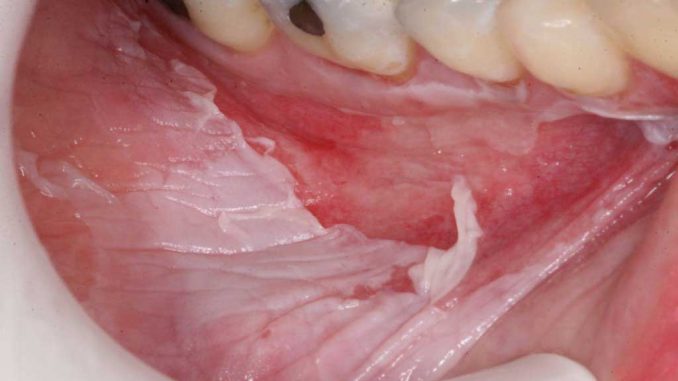

Ожог слизистой оболочки

Состояние возникает вследствие воздействия на слизистую спиртом, мышьяком, высокими температурами, агрессивными химическими средствами, слишком горячей пищей или напитками. В результате наблюдаются симптомы:

- появление волдырей, изъязвлений;

- при несвоевременном лечении – отмирание, или некроз тканей, инфицирование.

Через некоторое время обожженная область становится шершавой, на деснах возникают разного диаметра лопающиеся пузыри, которые превращаются в открытые глубокие раны. Весь процесс сопровождается постоянными болезненными ощущениями, усиливающимися при соприкосновении поверхности с пищей, водой.

Если лечение не начато своевременно, происходит отек, потемнение десны, кровоточивость, некроз.

Одна из наиболее распространенных травм ротовой полости – термический вид ожога десны или слизистой. Его получал несколько раз в жизни каждый человек. Достаточно просто сделать на бегу глоток горячего кофе или супа, чтобы почувствовать жжение и дискомфорт. Подобная проблема хорошо знакома хозяйкам, которые ежедневно пробуют пищу во время готовки и проверяют ее вкус. Из-за особого строения клеток эпителия, наполненного влагой, при попадании жара симптомы развиваются максимально быстро:

- На деснах выступают шишки, волдыри и пузыри, наполненные жидким содержимым. Они имеют разный размер.

- Поверхность становится шершавой и неприятной на ощупь: если провести пальцем, он не скользит.

- Возникает ноющая постоянная боль, которая становится сильнее при употреблении пищи или прикосновении.

- Когда пузырьки с экссудатом лопаются, образуются красные открытые ранки и эрозии.

Основные симптомы при химическом ожоге поверхности десны немного отличаются от термического. При этой форме у больного могут отсутствовать объемные волдыри, рана уходит вглубь и окружена опухшими тканями. При этом беспокоит жуткая боль, зуд внутри и другие неприятные симптомы.